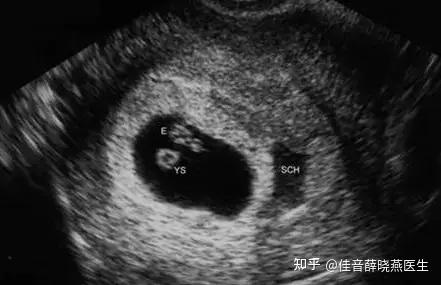

第1次:早孕期确认B超(通常在孕6-8周)

- 目的:

- 确认宫内妊娠: 排除宫外孕的可能性。

- 确认孕囊位置和数量: 看是单胎还是多胎。

- 核对孕周: 通过测量胎芽大小(头臀长),来推算准确的预产期,尤其是在月经不规律的情况下。

- 查看胎心搏动: 确认胚胎是否存活。

- 检查附件: 观察卵巢、输卵管等附件情况。

- 特殊情况: 如果有阴道出血、腹痛等异常情况,这次检查会提前进行。